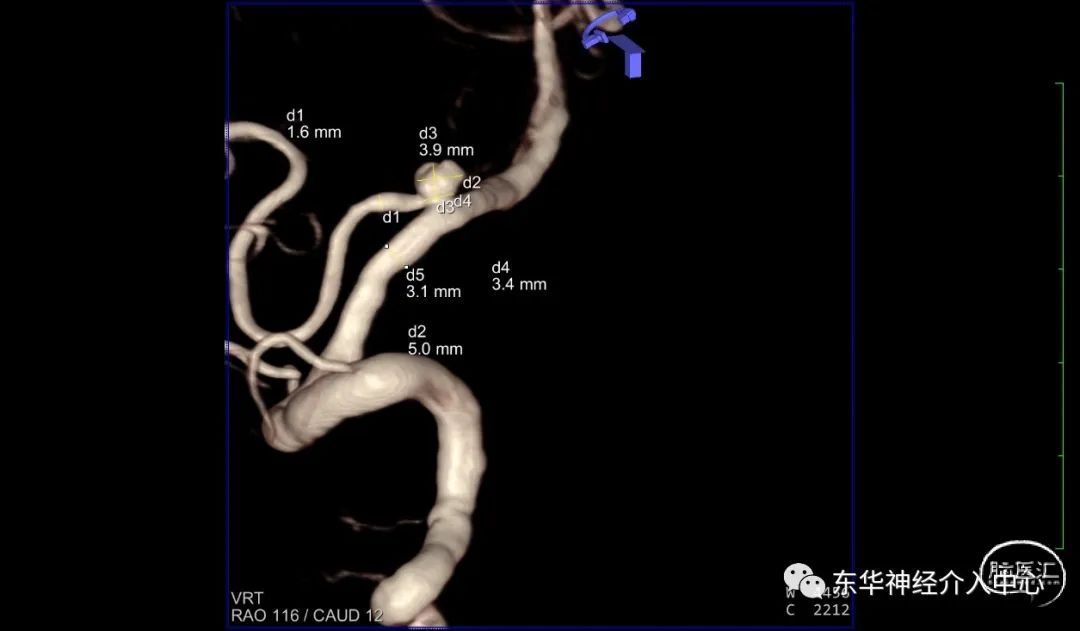

女性患者,高龄,68岁。突发头痛4小时入院。行头部CT+CTA 确诊为“自发性蛛网膜下腔出血,右侧PICA破裂动脉瘤 ”。家属选择介入治疗。术前根据CTA 的结果认为尽管动脉瘤是PICA 动脉瘤,但是应该是可以使用完成手术的,毕竟之前这个部位的动脉瘤也使用过支架辅助下成功手术过。尽管颈部CTA 提示同侧椎动脉开口狭窄、PICA 与椎动脉的夹角呈锐角,支架导管也是可以从对侧椎动脉翻山跨过双侧椎动脉汇合部到达PICA 内。手术尽管有难度但是应该可以完成的。如此信心满满的上手术台。但是造影后却郁闷了。发现手术难度大大的超过术前设想。

病人因为高龄、血管条件不好,到处硬化、斑块。同侧椎动脉开口狭窄,对侧椎动脉迂曲明显。PICA 从瘤颈发出。微导丝超选到位应该难度很大且风险极高。从对侧通过翻山越岭技术因为只有唯一的一根中间导管,所以只能硬着头皮从右侧椎动脉入路。

术后3D DSA动态显示栓塞满意、PICA血流无任何影响。